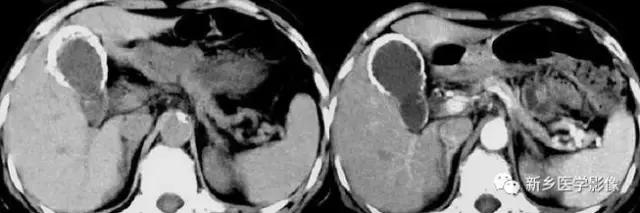

10、脾和肝肉芽肿

主要表现为点状的钙化,CT显示清晰,腹部平片有时候表现不明显。